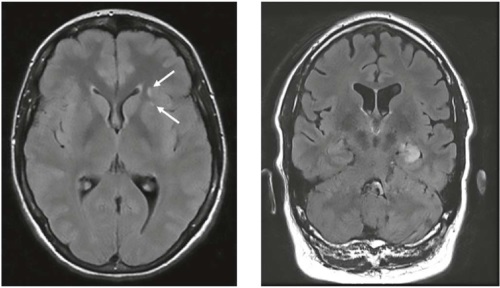

Аутоиммунные энцефалиты (АИЭ) представляют собой неинфекционные иммуноопосредованные воспалительные заболевания паренхимы мозга с частым поражением коркового или глубокого серого вещества с вовлечением или без вовлечения белого вещества головного мозга, мозговых оболочек или спинного мозга. Наиболее частыми клиническими синдромами АИЭ являются расстройства психики, поведения, когнитивных и вегетативных функций, двигательные нарушения, а также эпилептические приступы. Диагностику АИЭ может затруднять изолированная представленность психопатологической галлюцинаторно-бредовой и эмоционально-аффективной симптоматики, что может имитировать дебют идиопатического психического расстройства и требует определённой настороженности и повышенного внимания к данным анамнеза и оценке неврологического статуса. МРТ-паттерн лимбического энцефалита с одно- или двусторонним поражением медиальных отделов височных долей является типичным для АИЭ, однако возможны как нормальная МРТ головного и/или спинного мозга, так и вовлечение самых различных отделов головного мозга при разных подтипах АИЭ. Необходимо учитывать вероятность не только рецидивирующего течения АИЭ, но и возможность развития перекрывающихся синдромов АИЭ и других аутоиммунных расстройств, включая демиелинизирующие заболевания: рассеянный склероз, расстройства спектра оптиконейромиелита или заболевания, ассоциированные с антителами к миелин-олигодендроцитарному гликопротеину, — что требует более длительного наблюдения из-за риска рецидива аутоиммунных заболеваний.